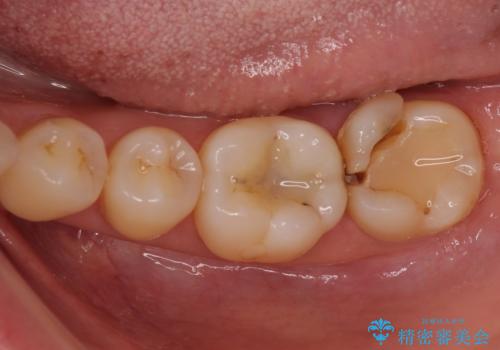

奥歯が割れた 神経が取り除かれた歯のセラミッククラウン治療

- 神経が取り除かれた歯が欠けてしまったとのことで来院された患者様です。

破折線が歯肉の中、深いところにまで及んでいる場合には歯周外科の適用となることを伝えた上で、補綴治療を行うこととしました。

破折部位を除去したところ、外科処置が必要な深さまで破折線が及んでいなかったため、速やかにジルコニアクラウンにて補綴を行うことになりました。